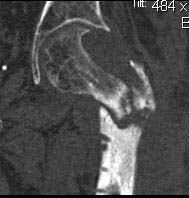

Re: Несращение проксимального отедла бедра, дефект головки

Вот еще снимки после и КТ.

Re: Несращение

кт